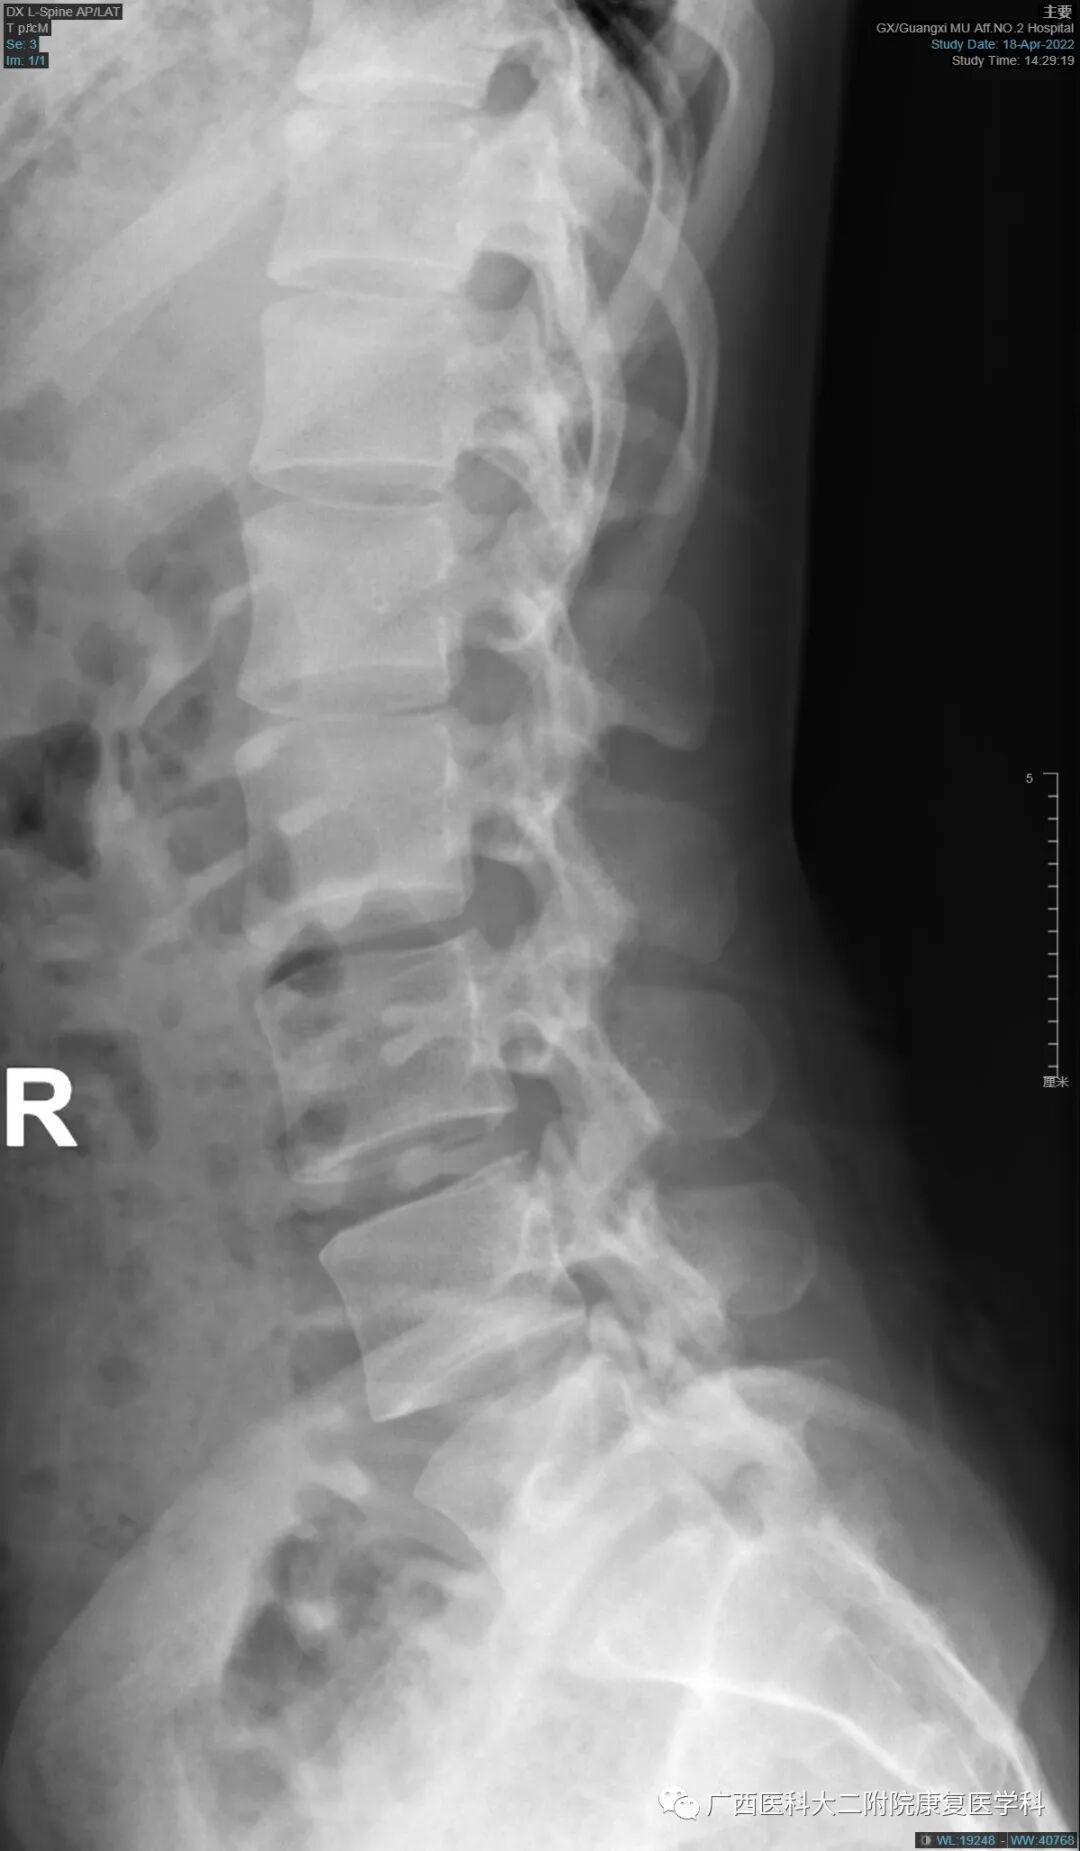

辅助检查:X线片显示L5右侧横突肥大,并假关节形成。

查体:腰椎生理曲度存在,腰肌紧张,L3-L4L4-L5棘上韧带处轻微压痛,无叩击痛,坐位前屈腰骶部有疼痛、躯干旋转有疼痛、屈颈试验(-)直腿抬高试验(-)。

X线